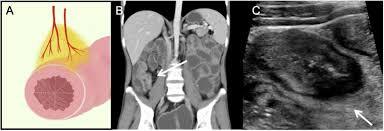

HD?

Diverticulite.

Diverticulite aguda à esquerda com aumento acentuado da ecogenicidade da gordura ao redor de um divertículo.